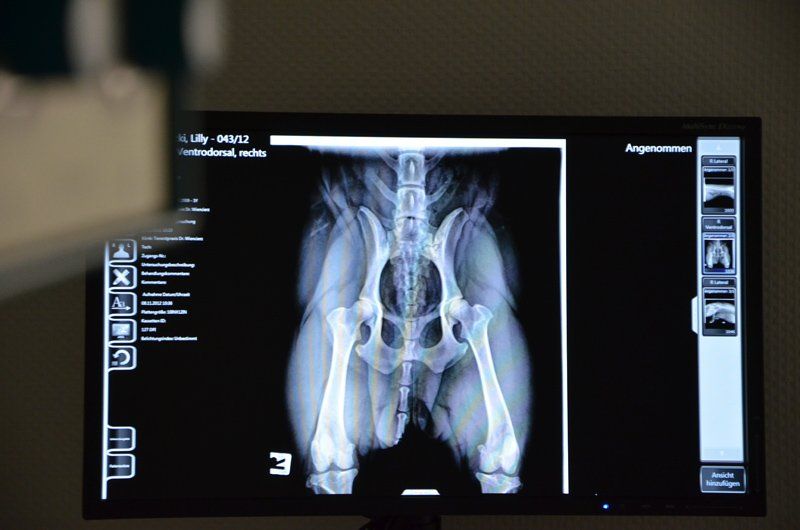

digitales Röntgen

Mit unserem Amadeo V-DR-System gelingt es,

Röntgenbildinformationen optimiert zu verarbeiten, die sofort nach der Aufnahme auf dem PC zur Verfügung stehen. Vorteile gegenüber dem herkömmlichen Filmsystem sind:

- geringere Manipulation und Röntgenbelastung der Patienten

- Der schnellere Zugriff auf die Bildinformation und

- Die hohe Bildqualität und damit verbesserte Diagnostik

Die Bildinformation steht sofort zur Verfügung und kann zum Beispiel an Fachkollegen versendet werden und/oder auf CD gebrannt dem Besitzer mitgegeben werden.